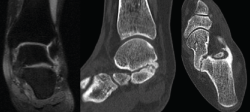

Figura 1. Segundo caso: coalición tarsal talocalcánea sinostótica bilateral. Pie derecho. Tomografía axial computarizada y radiografía.

Se trata de una paciente mujer de 18 años de edad, higienista dental, sin antecedentes patológicos de interés, que presenta pies planos valgos bilaterales dolorosos, el derecho de 23° y el izquierdo de 21° de valgo, por sinostosis calcaneoastragalina media en ambos pies. En ella observamos básicamente una clínica de dolor en el seno del tarso, con déficit de movilidad de la articulación subtalar en ambos pies. Se realiza estudio mediante radiografías de los pies y los tobillos en carga y TAC de ambos pies (afectación bilateral). Radiológicamente, las articulaciones tibioperoneoastragalina y subtalar están preservadas. Se diagnostica de coalición tarsal de tipo 4 de la clasificación de Rozansky(26). El balance articular es de: flexión = 45°; extensión = 20°; inversión = 0°; eversión = 0°. La escala de la AOFAS para el tobillo derecho presentaba una puntuación de 62 (20-37-5). Los ángulos radiológicos iniciales son: Moreau-Costa-Bartani interno = 141°; declinación talar = 18,4°; Meary = 6,3°; Kite = 25,6°; taloescafoideo = 48,3°.